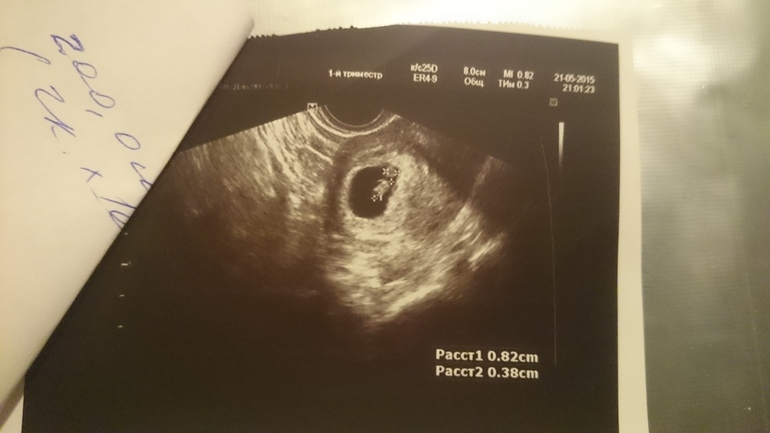

Второе УЗИ

Сходила на очередное УЗИ) Эмбрион на месте, шевелится и отбивает сердечком 140 ударов в минуту:))))

Срок малышу поставили чуть меньше чем по месячным. По месячным сегодня ровно 7 недель, по УЗИ 6+5. Но это даже к лучшему, так как ПДР сразу после нового года, а под куранты я рожать не хочу:)))

Под катом результаты и снимки с УЗИ